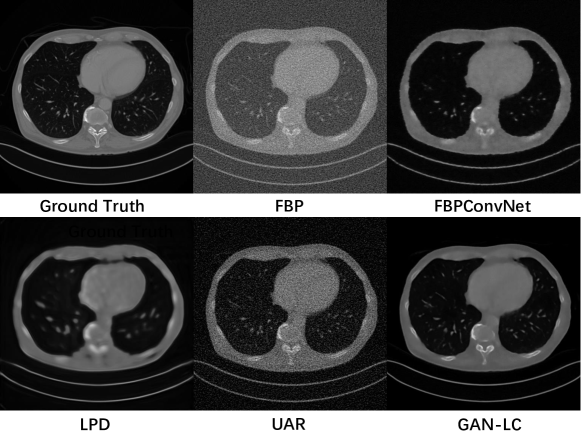

We consider several existing popular algorithms for comparison. (1) FBPย [12]: the classical filter backward projection on low-dose sinograms. (2) FBPConvNetย [11]: a direct inversion network followed by the CNN after initial FBP reconstruction. (3) LPDย [1]: a deep learning method based on proximal primal-dual optimization. (4) UARย [22]: an end-to-end reconstruction method based on learning unrolled reconstruction operators and adversarial regularizers. Our proposed method is denoted by GAN-LC. We set for the optimization objective in equationย (7) during our training process. Following most of the previous articles on 3D CT reconstruction, we evaluate the experimental performance by two metrics: the peak signal-to-noise ratio (PSNR) and the structural similarity index (SSIM)ย [33]. PSNR measures the pixel differences of two images, which is negatively correlated with mean square error. SSIM measures the structure similarity between two images, which is related to the variances of the input images. For both two meansures, the higher the better.

Table 1 presents the results on the Mayo-Clinic dataset, where the first row represents different parameter settings (i.e., the number of uniform views , the number of detectors and the standard deviation of Gaussian noise ) for simulating low-dose sinograms. Our proposed approach GAN-LC consistently outperforms the baselines under almost all the low-dose parameter settings. The methods FBP and UAR are very sensitive to noise; the performance of LPD is relatively stable but with low reconstruction accuracy. FBPConvNet has a similar increasing trend with our approach across different settings but has worse reconstruction quality. To evaluate the stability and generalization of our model and the baselines trained on Mayo-Clinic dataset, we also test them on the RIDER dataset. The results are shown in Table 2. Due to the bias in the datasets collected from different facilities, the performances of all the models are declined to some extents. But our proposed approach still outperforms the other models for most testing cases.

To illustrate the reconstruction performances more clearly, we also show the reconstruction results for testing images in Figure 3. We can see that our network can reconstruct the CT image with higher quality. Due to the space limit, the experimental results of different views and more visualized results are placed in our supplementary material.